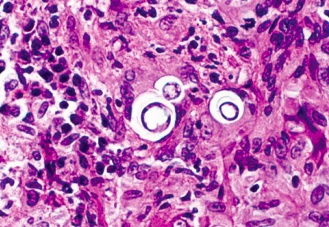

macrophage cage: Histology of macrophage with intracellular oval bodies. KOH stain

puddle: Macrophage with histoplasma inside, smaller than both RBC/macrophages